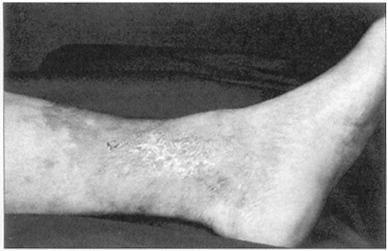

(1)主诉 静脉曲张(图59)的病人的主诉为其腿部静脉的外观、腿痛或腿部溃疡(图60)、血栓性静脉炎、出血、曲张性湿疹(图61)和踝部水肿。

图61 静脉曲张所致的湿疹

踝部皮肤褐色深染是好现象。静脉曲张能导致踝部周围湿疹,湿疹能遍布身体的其他部位。最令人关注的是,皮肤变粗,色素沉着和皮肤过度角化,他们会逐渐发展成严重的慢性静脉回流不畅和溃疡。